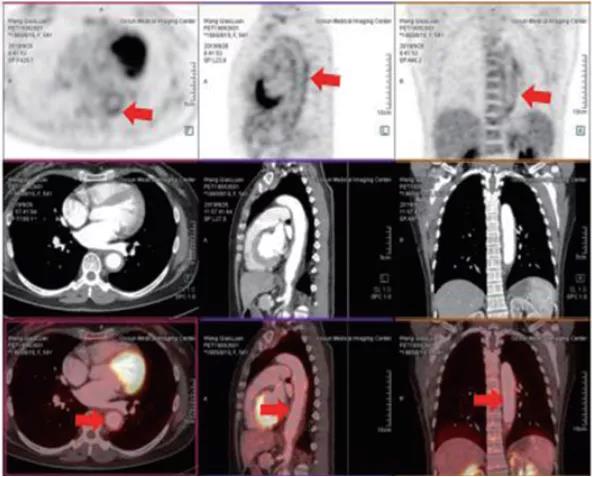

病例圖

?PET/CT在全身腫瘤的早期篩查、早期診斷及良惡性鑒別上、惡性腫瘤的分期、分級、尋找腫瘤原發(fā)病灶、評估療效及監(jiān)測腫瘤復發(fā)等具有重要價值。

一、腫瘤疾病的應用

1、腫瘤的早期診斷和鑒別診斷

2、對惡性腫瘤進行更準確分期,全面了解全身病變情況

3、已發(fā)現(xiàn)腫瘤轉移者,尋找原發(fā)灶

?精準:本設備是新一代PET/CT,圖像重建矩陣可達400×400,其分辨率達到毫米;其FlowMotion掃描技術提供極精細器官細節(jié)顯示,并對病灶提供精確的可重復定量分析;顯著提高了微小病灶的檢出和確診率。

?全 面:PET/CT是通過血管內注射示蹤劑,采用動態(tài)連續(xù)掃描全身,動態(tài)數(shù)據(jù)分析,跟蹤檢查精準定位,全身病變無處遁形。?快 速:本設備采用流式掃描技術,在3-5分鐘可以完成高質量的全身掃描,具有掃描速度快、靈敏度高的特點,可快速檢查全身,提高舒適度和診斷效率。